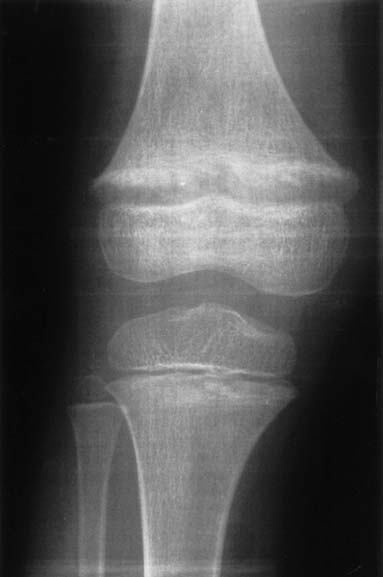

A 5-year-old girl was referred for further diagnostic work-up of rickets and bilateral nephrocalcinosis. She is the first child of healthy unrelated parents. She was born after an uneventful pregnancyat 40 weeks gestation, with a body weight of 2,680 g. Body height and weight remained below the 3rd percentile,she was reported to drink a lot, and psychomotor development was normal. When investigations were carried out for short stature,rickets and bilateral medullary nephrocalcinosis were observed by both U/S and X-ray. The girl has two sisters, aged3 years 6 months and 1 year 6 months, respectively, who are in good health to date. At presentation, body height was 96 cm and weight 13 kg. Blood pressure was 106/50 mmHg. Physical examinationwas normal except for large wrists, moderate genu valgum,and mild femoral bowing.Blood chemistry yielded the following information: urea (52 mg/dl) and creatinine (0.8 mg/dl), total calcium (10.7 mg/dl), magnesium(1.8 mEq/l), phosphate (1.6 mg/dl), and alkaline phosphatase (909 IU/l), parathyroid hormone (PTH) (<0.2 pg/ml) (normal 10–60) and 1,25-(OH)2 vitamin D (79 pg/ml) (normal 18–45). Serum electrolytes,albumin, transaminases, and uric acid were within normal ranges.Urine microscopy showed white cells but no erythrocytes. A24-h urine collection yielded 430 mg of protein per 1.73 m2 and 6.2 mg/kg calcium; excretion of uric acid, amino acids, and oxalate were normal and there was no glucosuria. Urinary β2 microglobulin/creatinine ratio was 1,312 μg/g. The maximal urinary osmolality was 304 mosmol/kg water under DDAVP stimulation. Bone X-rays showed metaphyseal lesionstypical for rickets (Fig. 1); bone age was 5 years. Renal U/S confirmed pronounced bilateral medullary nephrocalcinosis. The patient had been investigated at the age of 1 year because of poor weight gain. At that time, serum calcium was 12.1 mg/dl,phosphate was 3.9 mg/dl, and serum creatinine 0.6 mg/dl. She hadtaken vitamin D supplements (300 IU daily) up to the day of diagnosis.